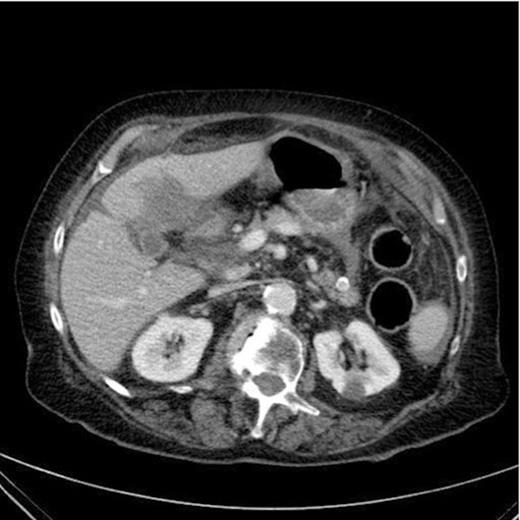

A CT scan of the abdomen and pelvis was requested which revealed inflammation surrounding the anterior of the stomach, a large irregular thick-walled collection arising from the fundus of the gallbladder, free fluid around the liver, spleen and paracolic gutter. Appearances were consistent with gallbladder perforation.

CT Scan demonstrating a thick walled gallbladder with free fluid in the paracolic gutter and a collection in the porta hepatis

It is unclear from the CT images whether the cyst is contained within the gastric cavity. Malignancy was also a potential concern at this stage.